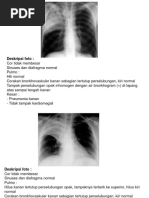

Hasil pemeriksaan Thorax PA:

- Posisi simetris, kondisi film cukup, inspirasi cukup

- Perselubungan inhomogen lapangan tengah paru kanan

- Tidak tampak pemadatan kedua hilus

- Cor : bentuk dan ukuran normal

- Kedua Sinus dan diafragma baik

- Tulang-tulang intak

Kesan : Pneumonia Dextra